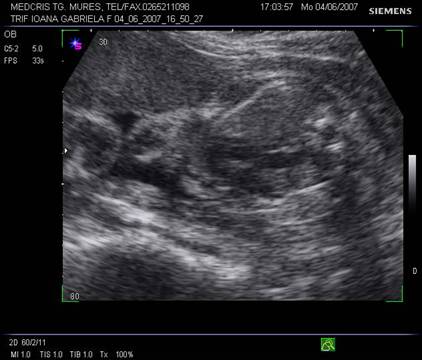

Fig. nr. 249. Hidrocefalie interna unilaterala aparuta la 28 sapt si cu evolutie rapida, postpartum se confirma suspiciunea de diagnostic: hemoragie cerebrala